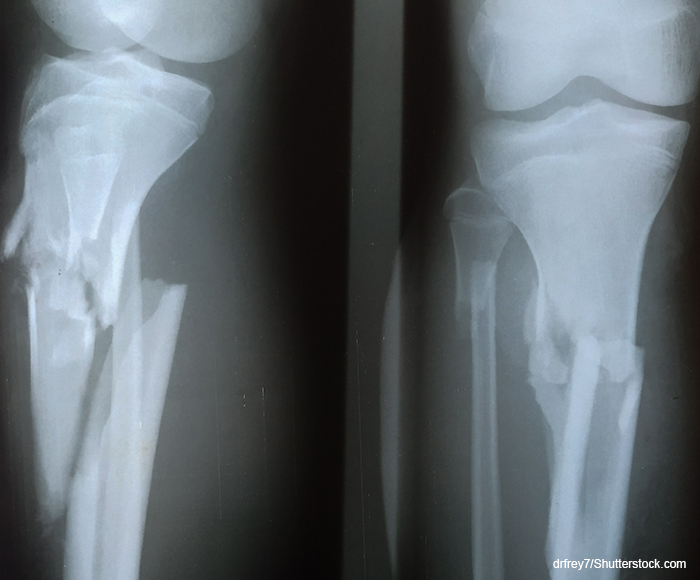

“I am proud of Dr. Rivera’s and LSU Health New Orleans’ contributions to this landmark study published in such a prestigious journal,” says Dr. Zura.The authors highlight WHO estimates of millions of patients worldwide each year who have surgical site infections. The inherent risk of using fracture fixation in a contaminated or dirty wound is realized in about 10% of open fractures developing surgical site infections. Orthopaedic surgical procedures have the highest infection rate, greater than 20% for severe open tibia shaft fractures.

Previous reviews of general surgery, obstetrics and gynecology trials suggested the superiority of chlorhexidine over iodine. The Aqueous-PREP multiple-period, cluster-randomized, crossover trial included 14 hospitals in Canada, Spain and the United States and 1,638 adults who underwent surgery for an open extremity fracture. It found that the odds of surgical site infection or unplanned fracture-related reoperations did not differ between patients assigned to receive skin antisepsis with aqueous 10% povidone or aqueous 4% chlorhexidine gluconate. The authors wrote, “Our findings contrast the superiority of chlorhexidine in alcohol that has been shown in clean or clean-contaminated surgery.”The authors note their findings could have particular relevance to low- and middle-income countries, where both antiseptic solutions might not be readily available or procuring both products is unnecessarily costly.